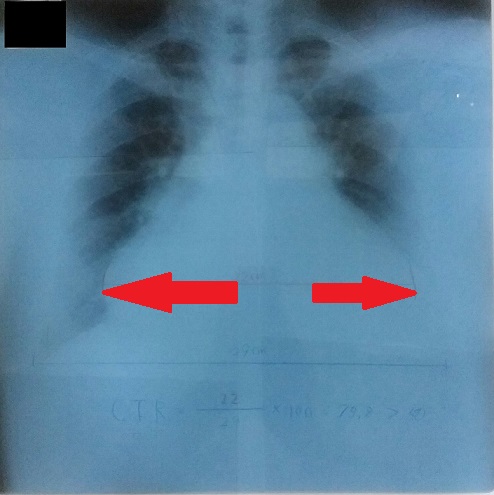

<胸部エックス線>

正面像:心拡大 心・胸郭比増大

肺水腫の所見の検索

①心陰影の拡大(心・胸郭比↑)CTR=75.8%(基準:50%未満)

②上肺野の血管陰影の増強

③肺門部を中心としたうっ血(バタフライ陰影)

以上を認めましたが、胸水貯留をはじめKerley’s B line,vanishing tumorなどの所見は認めませんでした。